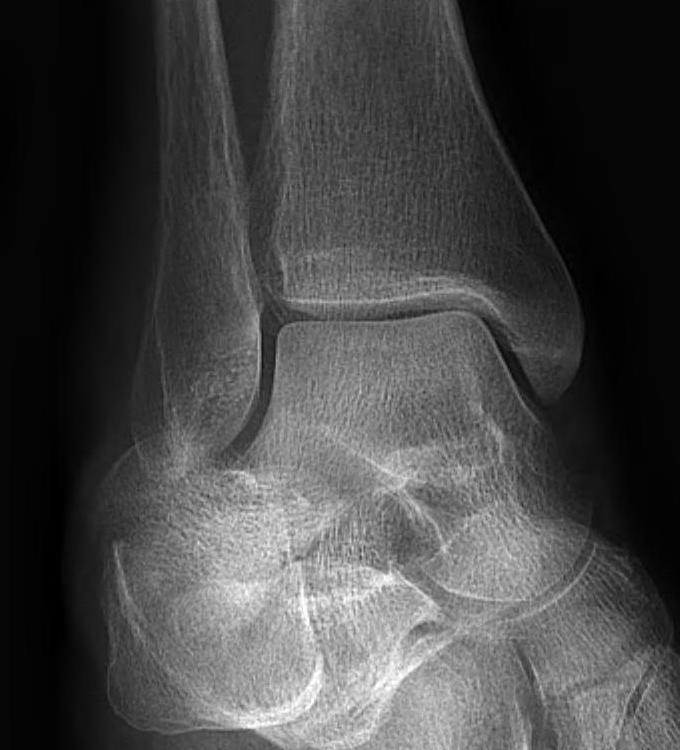

X-ray assessment

3 standard views

AP / Lateral / Mortise

Mortise

- AP with foot internally rotated

- should be symmetrical space around talus

Ankle Mortise ViewMortise